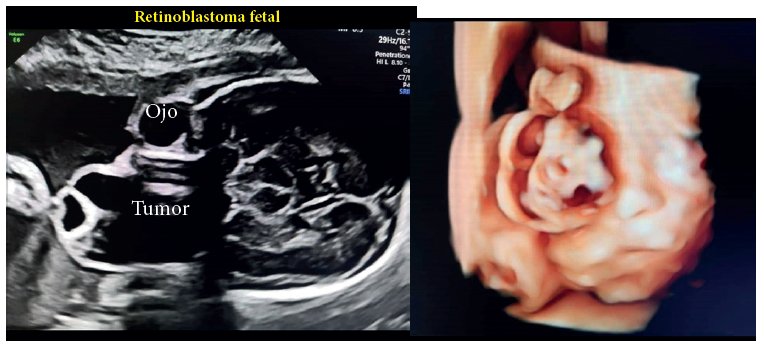

Retinoblastoma Fetal por Ultrasonografía

Fetal Retinoblastoma by Ultrasonography

Retinoblastoma fetal es un tipo de cáncer ocular que afecta a la retina, la capa interna del ojo.

Las células nerviosas de la retina captan la luz y envían imágenes al cerebro.

En el corte coronal del cráneo y parte del macizo facial, se observa protrusión de masa semisólida de predominio quístico hacia anterior que ocupa toda la cavidad orbitaria derecha, acompañada de desplazamiento en forma y estructura del globo ocular derecho.

En la imagen 3D, desde el punto de corte coronal. Se evidencia deformación de la estructura del globo ocular derecho con exteriorización de la masa que agranda el mismo de la lesión de manera irregular, con desplazamiento de los párpados y a su borde medial.